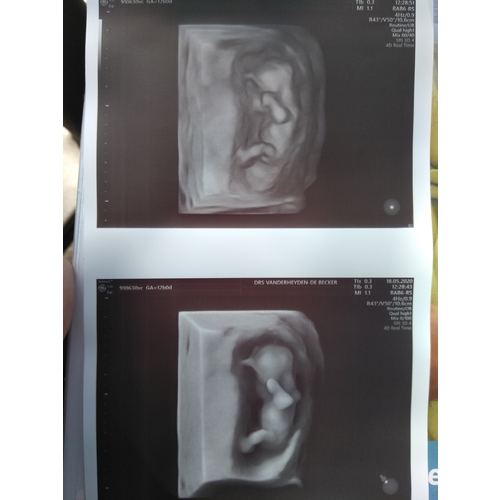

Mijn gynaecoloog heeft van een van de twee kindjes in m'n buik een 3D echo kunnen maken. Het andere kindje zat met de rug naar voor dus daar kon ze geen mooi beeld van nemen.

Mijn gynaecoloog heeft van een van de twee kindjes in m'n buik een 3D echo ...